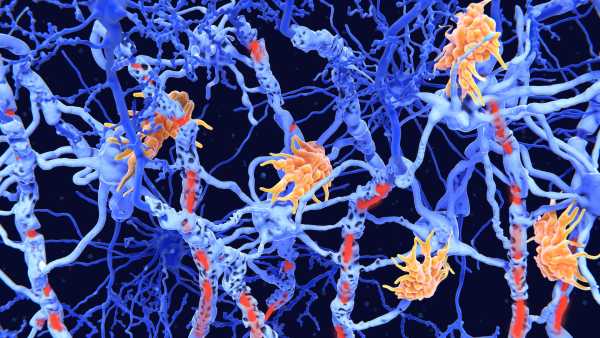

Розсіяний склероз (РС) – це аутоімунне захворювання, яке викликає запалення в головному та спинному мозку. Це запалення пошкоджує мієлінові оболонки – ізоляцію, яка огортає довгі «дроти» нервових клітин – і призводить до таких симптомів, як біль, втома, оніміння або слабкість, а також проблеми із зором або рухом.

Відомо, що у людей з розсіяним склерозом (РС) високий рівень імунних клітин, які називаються цитотоксичними Т-клітинами, що зазвичай допомагають знищувати ракові та інфіковані мікробами клітини. Однак при РС ці клітини накопичуються в ділянках з видимим пошкодженням мієліну, але роль, яку ці клітини відіграють у цьому захворюванні, досі залишалася значною мірою загадкою.